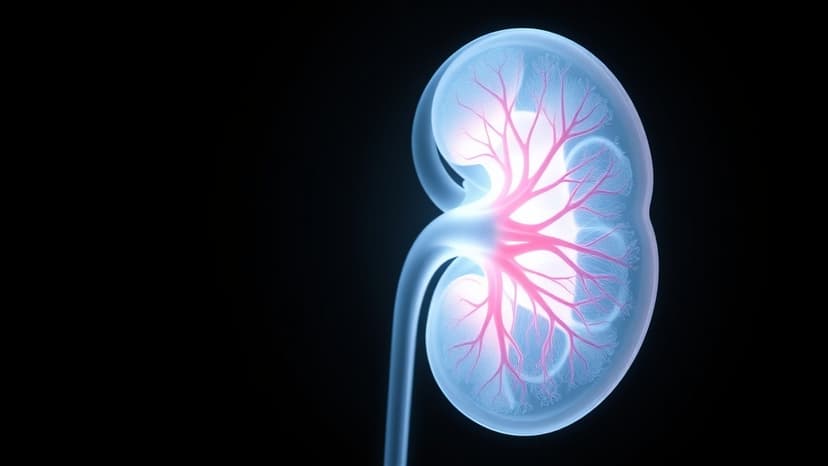

Kidney Disease: 90% Unaware of Silent Threat

Chronic kidney disease (CKD) is a widespread condition, with an estimated one in ten individuals worldwide affected, yet a staggering 90% remain unaware of their illness. This lack of awareness stems from the fact that substantial kidney function, up to 90%, can be lost before any noticeable symptoms arise, leading to late diagnoses.